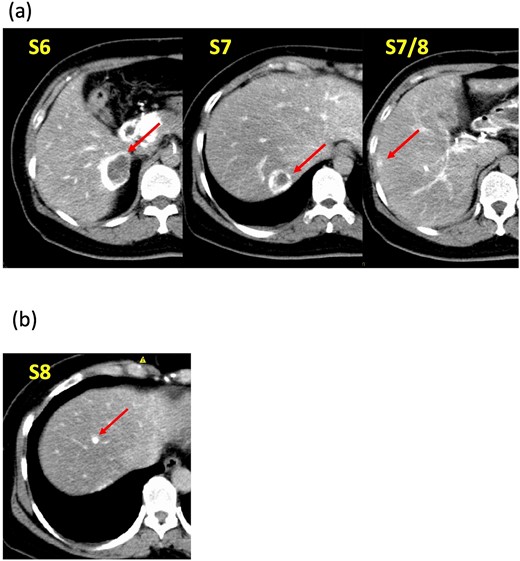

A 52-year-old woman was admitted to our hospital for the evaluation and treatment of multiple cystic liver tumors. Two years earlier, dynamic computed tomography (CT) had detected multiple cystic tumors in segments 6 (S6) and 7 (S7), which were subsequently monitored (Fig. 1a). The patient showed no symptoms; laboratory tests for tumor markers such as α-fetoprotein, protein induced by vitamin K absence or antagonist-II, carcinoembryonic antigen, and carbohydrate antigen 19–9 were within normal ranges. Dynamic CT identified two low-density tumors with peripheral enhancement in the portal phase, featuring cyst-like internal septa (Fig. 1b), which showed slow enlargement over 2 years. Magnetic resonance imaging (MRI) using gadoxetic acid (gadolinium-ethoxybenzyl-diethylenetriamine pentaacetic acid; EOB Primovist®) revealed that tumors appeared as low intensity signals on T1-weighted imaging and high intensity signals on T2-weighted imaging and diffusion-weighted imaging. Additionally, a 7-mm lesion was observed at the S7/8 boundary (Fig. 2a and b). Positron emission tomography-CT (PET-CT) showed abnormal uptake in S6 and S7 tumors but not in the S7/8 lesion (Fig. 3). CT during hepatic arteriography (CTHA) demonstrated well-contrasted tumors at the periphery, with no contrast enhancement in the center (Fig. 4a). Moreover, CTHA detected a new tumor in S8, displaying clear and uniform contrast but not visible with other imaging modalities (Fig. 4b).

Computed tomography during hepatic arteriography findings. (a) Known tumors in S6, S7, and S7/8 exhibit peripheral contrast enhancement but lack contrast in their centers. (b) The new tumor in S8 displays a distinct, uniform contrast effect.